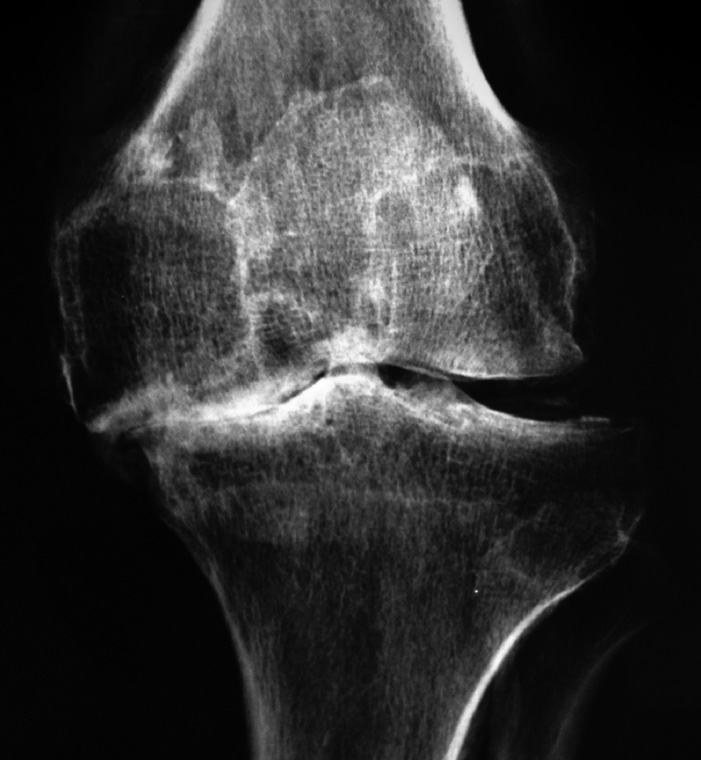

Sin embargo, el desgaste por lesiones del cartílago traumáticas, por envejecimiento (osteoartritis), por secuelas de fracturas o traumatismos, una mala alineación de la articulación o no resueltas en tiempo y forma, alteran dicha armonía en la función articular provocando de manera progresiva dolor, rigidez articular, debilidad muscular y disminución de la función.

La principal causa del dolor crónico de la rodilla que condiciona discapacidad por desgaste articular es la osteoartrosis, sin embargo, la artritis reumatoide y el desgaste articular postraumático, son causas frecuentes de lesión del cartílago de manera extensa y acelerada.

• La artritis reumatoide es una enfermedad sistémica que se caracteriza por inflamación crónica de las articulaciones, provocando que la membrana que las envuelve se engruese.

• Habitualmente la inflamación crónica y el engrosamiento de los tejidos dañan al cartílago articular. El desenlace final es dolor, deformidad y rigidez de la articulación